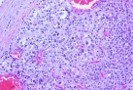

Figure 8.MEN1 syndrome enunciating an adrenocortical carcinoma with features of malignancy such as nuclear hyperplasia, hyperchromasia and pleomorphism16.

MEN1 syndrome enunciating an                 adrenocortical carcinoma with features of                 malignancy such as nuclear hyperplasia,                 hyperchromasia and pleomorphism16.